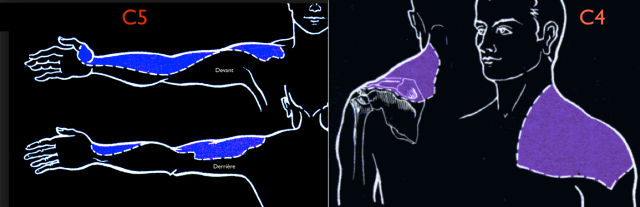

Le patient décrit une douleur locale qui peut irradier dans le trapèze (dermatome C4)

(contrairement aux douleurs causées par un trouble de l’épaule ICI ou de la colonne cervicale ICI)

Une entorse de l’articulation acromio-claviculaire peut exister en même temps qu’une inflammation de la bourse (bursite). Dans ce cas, les douleurs projetées se feront dans le dermatome C4 ET dans le dermatome C5

Dermatome C4 et C5

Une lésion importante de l’acromio-claviculaire est toujours traumatique et c’est important pour expliquer vos douleurs : dermatome C4 et C5.

Mais l’atteinte de l’articulation AC provoque des douleurs dans le dermatome C4.

Si vous avez aussi des douleurs dans le dermatome C5, il se pourrait que le traumatisme ait provoqué une bursite (dite traumatique) qu’on peut facilement mettre en évidence à l’examen clinique et à l’échographie.